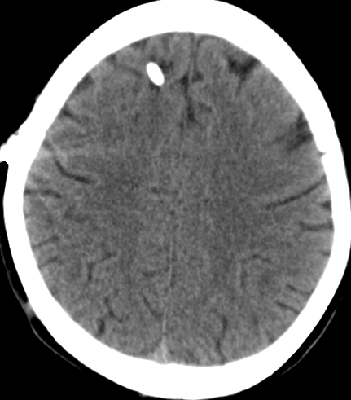

2013-8-2 CT

腰穿脑压240